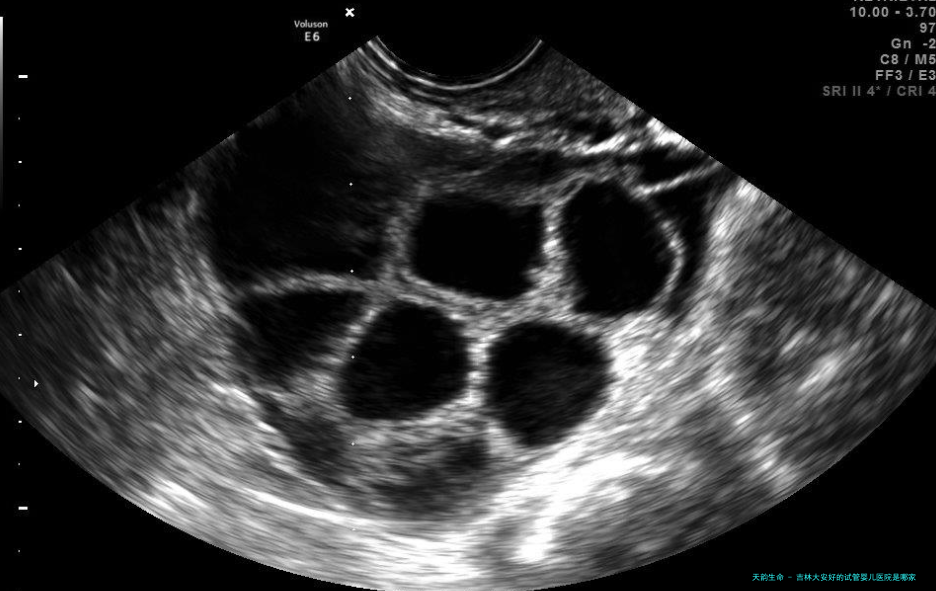

吉林大安好的试管婴儿医院是复兴医院孕育中心。复兴医院孕育中心是吉林省专业做试管婴儿的专业机构,前身是1994年由复兴泌尿外科中心分离出的恢复孕育中心,成立以后服务于国内外许多客户,成为一个特性鲜明的当代化孕育机构,拥有超过二十名,其中10位医生技术崇高高贵的孕育相关的专业人士,从最先的辅助生殖技术开展着至今的无痛触受胚胎移植技术等治疗,已经有不计其数的婴儿出生成功,为众多非育龄夫妻和单身母亲完成了美满愿望。复兴除了享有高技术能力外,还有高端装置设备及特殊的服务理念、完备的医疗体系,让每一个客户都能感受到家的温暖。

吉林大安好的试管婴儿医院是中信和睦医院。位于吉林省大安市,有着超过30年的受孕临床治疗经验,是一家大型综合性医院。该医院坐落在泰山路774号,具备超过十年的试管婴儿操作经验,并具备国际前沿的医疗科技,如健康打算、无痛生育、卵子保存等,可以帮助女性成功受孕。咨询时首先由医生进行全面访谈,囊括个人及家庭病史、体魄检查、精液剖析等,再次结合每一双夫妻的年龄、患者的特殊情况,进行针对性的诊疗计划。此医院拥有超群的器械,包括最新型的试管受孕设备和先进的卵子保存技术,以满足不同患者的需求,为夫妇两边提供专业的、多元化的诊断服务,可以有效帮助病患达到具体的治疗目标。此外此医院还聘任有专业学识、有丰厚受孕经验的医生,及时和准确地给门诊疗意见,可以让夫妻成功地完成试管就诊。